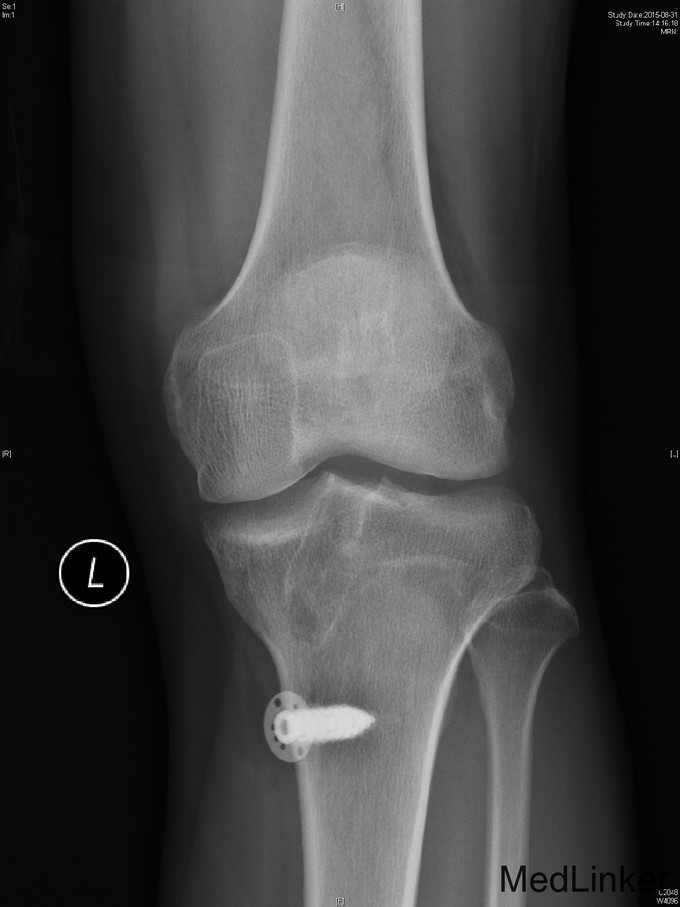

主诉:左膝前交叉韧带重建术后,要求取内固定 。 现病史:患者9年前运动时扭伤左膝关节,后出现左膝不稳、左下肢乏力。患者当时来我院就诊,诊断左膝前交叉韧带损伤,行左膝前交叉韧带自体重建术。患者自觉术后恢复良好,未规律行康复锻炼。2年前患者自觉左膝行走时偶有交锁伴疼痛。今患者为取左下肢内固定物来我院就诊。

查体:右下肢、双上肢肌力及活动度正常。左股四头肌萎缩,肌力V-级。左膝关节无明显肿胀,关节ROM尚正常,关节过伸过屈时无疼痛。髌骨活动度正常,髌周无压痛。浮髌试验(-),压磨髌(-)。麦氏征(+)。关节间隙压痛(+)。ADT(+-),Lachman征(+-),侧方应力实验(-)。双下肢无明显感觉异常。 左膝X线示:左膝术后改变。 注:患者因体内内固定无法进行核磁共振检查,这也是患者强烈要求取出内固定的原因。

诊断:左膝前交叉韧带重建术后,左膝半月板损伤。 治疗:左膝内固定取出术+左膝关节镜下探查+左膝前交叉韧带皱缩+内侧半月板成形术